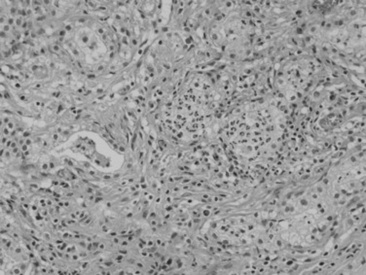

Fungal hyphae may be identified in airway fluid or in impression smears obtained from biopsied masses. Clinicians must be careful in attributing significance to the presence of fungal elements in a TTA. Fungal hyphae are often present either free or in large mononuclear cells in tracheal aspirates from healthy horses.90 A study of healthy thoroughbred racehorses showed that 70% had fungal elements detected in their tracheal aspirates.92 None of the horses from either study had other evidence of fungal pneumonia. Barn fungus such as Alternaria species are nonpathogenic and rarely incite an inflammatory response in the host. The organisms often have a blocklike appearance and may be colored (Fig. 31-18, A and B). A normal predominance of macrophages, lymphocytes, and nondegenerate neutrophils (<5% to 10%) would be expected.

image image

Fig. 31-18 Alternaria species from transtracheal wash specimens obtained from healthy horses. A, An extracellular spore (arrow) with several macrophages, squamous cell (indicative of pharyngeal contamination. B, Intracellular spores (arrow) within binucleated macrophage.

Courtesy Elizabeth Welles, Auburn University, Ala.

To be significant cytologically, large numbers of fungi should be involved in the inflammatory process within the lung. With fungal pneumonia, aspirates may contain predominately neutrophils that often are degenerate and may contain intracellular fungal hyphae. If processing of the sample is delayed, extracellular fungi may be phagocytized, which confuses the interpretation. Some fungi have characteristic morphologic features that can permit an early presumptive identification (Table 31-5).